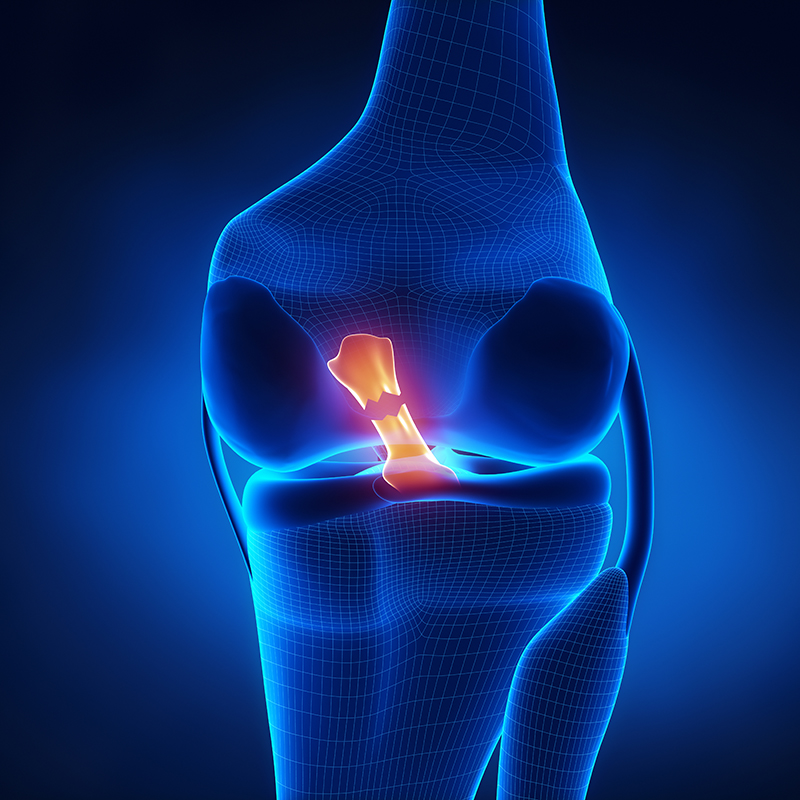

REKONSTRUKCJA ACL (WIĄZADŁA KRZYŻOWEGO PRZEDNIEGO) STAWU KOLANOWEGO

Jest zabiegiem wskazanym u wszystkich osób z jego całkowitym lub częściowym uszkodzeniem przy obecnych objawach niestabilności stawu kolanowego. Rekonstrukcja więzadła krzyżowego przedniego jest procedurą wykonywaną metodą artroskopową co daje wiele korzyści: małoinwazyjne dostępy-małe blizny, szybszy powrót do sprawności, mniejsze dolegliwości bólowe pooperacyjne oraz krótszy czas hospitalizacji i rehabilitacji. Do rekonstrukcji wykorzystywane są przeszczepy własne pacjenta (ze ścięgna mięśnia półbłoniastego, więzadła właściwego rzepki lub rozcięgna mięśnia czworogłowego) lub więzadła sztuczne - wybór przeszczepu jest dobierany indywidualnie do potrzeb pacjenta. Dodatkowo w naszej klinice wykonuje się rekonstrukcję metodą hybrydową, dedykowaną osobom, którym zależy na maksymalnym skróceniu okresu rehabilitacji po zabiegu.

Wskazania do zabiegu to m.in. :

- całkowite uszkodzenie więzadła krzyżowego przedniego

- częściowa rekonstrukcja więzadła krzyżowego przedniego